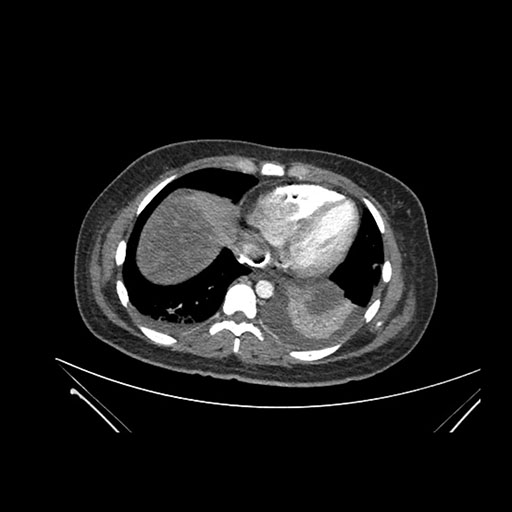

Axial Arterial

Axial Venous